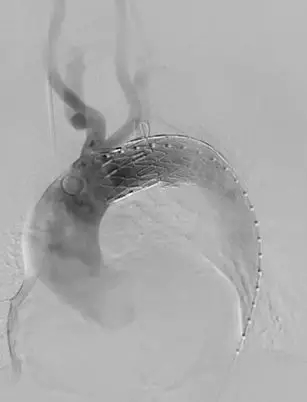

(左锁骨下动脉支架植入后造影)

CT测量显示,近端锚定区直径为30mm,取Ankura™34200支架输送到病变位置,根据Ankura支架大弯侧8字形mark点和加强筋,使其准确锚定于左颈总动脉远端,便于原位开窗。彩神在线网信彩票-彩神通免费版下载-彩神8争霸vlll-彩神购彩购彩大厅-彩神软件陆立根免费版-彩神ll争霸3-彩神ll彩神8-彩神ll争霸彩票-拼搏在线彩神网网页版科技Ankura™主动脉覆膜支架主体的e-PTFE膜设计非常适合原位开窗,其可穿透性佳,用普通的球囊即可扩开,不需要使用切割球囊,且球囊扩开后无撕裂现象,可以降低内漏的发生率。然后采用彩神在线网信彩票-彩神通免费版下载-彩神8争霸vlll-彩神购彩购彩大厅-彩神软件陆立根免费版-彩神ll争霸3-彩神ll彩神8-彩神ll争霸彩票-拼搏在线彩神网网页版Fustar™可调弯鞘和穿刺球囊系统进行左锁骨下动脉开窗,彩神在线网信彩票-彩神通免费版下载-彩神8争霸vlll-彩神购彩购彩大厅-彩神软件陆立根免费版-彩神ll争霸3-彩神ll彩神8-彩神ll争霸彩票-拼搏在线彩神网网页版穿刺球囊系统由球囊和穿刺针组成,充盈的球囊可以使穿刺针保持在分支血管的中央位置。由于此患者左锁骨下动脉与主动脉为锐角弓,穿刺破膜定位比较困难,彩神在线网信彩票-彩神通免费版下载-彩神8争霸vlll-彩神购彩购彩大厅-彩神软件陆立根免费版-彩神ll争霸3-彩神ll彩神8-彩神ll争霸彩票-拼搏在线彩神网网页版Fustar™鞘头端可以调整角度,使其头端与主体覆膜尽量处于直角状态,同时提供足够的支撑力,能够提高开窗成功率和效率。穿刺完成后,采用3mm和8mm的球囊对穿刺破口逐步进行扩张,最后在左锁骨下动脉植入覆膜支架。术后造影显示,支架形态良好,分支血流通畅,无内漏。